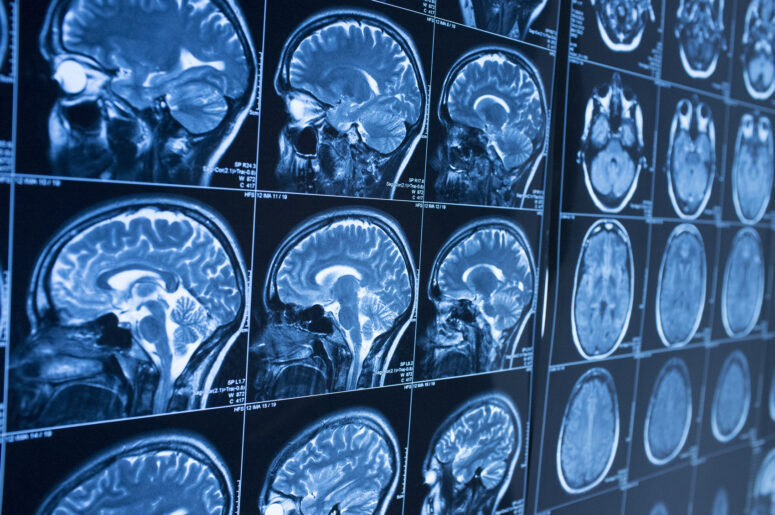

The brain is a delicate organ that can be injured in any number of ways including sports injuries, car accidents, falling objects, and infections. The key to managing brain injuries is to control what you can, namely how you treat yourself after incurring the injury. Major brain damage symptoms may develop after the accident event because the victim did not take proper care with returning to their routine. Your brain requires rest and relaxation to put itself back together after a major injury.

Treating mild brain injuries usually means managing the symptoms like pain relievers to handle headaches. However, this does not mean that you can pop a pill and be done with the process. It is difficult to draw a direct line between “mild” and “severe” brain injuries. Often it is possible for an apparently mild concussion to develop into a severe brain injury. Usually, this will not occur without some initial warning signs.

The brain is a fascinating organ because it controls everything that makes a person who they are. A major injury to the brain can change that person’s behavior. In fact, it is these changes in behavior that are the key to noticing if a brain injury is more severe than initially diagnosed. Pay attention for moments of intense anger, sadness or confusion that are atypical for the person injured. These could be signs of a more serious problem.

Severe brain injuries threaten the person’s life, so treatment is divided into two phases: stabilization and rehabilitation. Stabilization is limited to ensuring that major body functions remain operational. Rehabilitation happens after the person is stabilized and focuses on helping the victim recover their mental faculties.